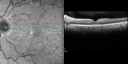

SPECTRALIS-SD-OCT SCAN: The OCT scan shows gaps and cysts in the retina in both eyes with a normal central foveal thickness and photos confirm clinical findings.